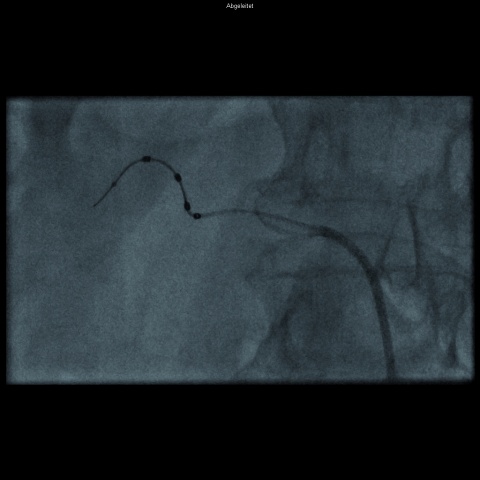

Im Vergleich zu Abbildung 2 sind hier vier Elektroden (dunkel

im Bild) spiralförmig auf einem Katheterdraht angeordnet. (Symplicity

Spyral-Katheter)

WMM_

Neben der Anwendung von Radiofrequenzenergie mittels einer „Single-point-Läsion“ (Abbildung 2) haben sich mehrere verschiedene Techniken entwickelt. So sind auch Katheter verfügbar, welche mit mehreren Elektroden besetzt sind, wie etwa das EnligHTN-System (St. Jude Medical, St. Paul, MN, USA) [23] oder das Symplicity Spyral-System von Medtronic (Min-neapolis, MN, USA) (Abbildung 3) [24]. Ebenso ist eine einmalige, zirkumferenzielle Ablation mittels des Paradise-Systems (ReCor Medical PARADISE® Inc., Palo Alto, CA, USA) möglich. Hierbei handelt es sich um einen gekühlten Ballon mit Nutzung von Ultraschall als Energieform, um die sympathischen Nervenfasern zu veröden [25]. Daneben gibt es noch weitere, weniger verbreitete und weniger erforschte Methoden, wie etwa die Kryoablation [26] oder die Denervation mittels perkutanem Ultraschall [27]. Randomisierte Studien, welche die verschiedenen Systeme in Bezug auf die resultierende Blutdruckreduktion testen, existieren derzeit noch nicht. Bisher wurden allerdings zwei Studien publiziert, bei denen sich ein blutrucksenkender Effekt durch eine zweite Prozedur mit einer anderen Energieapplikationsform zeigte [26, 28].

Abbildungen 1 und 2: Stabsarzt Dr. Thomas Okon, BwKrhs Berlin und Herzzentrum Leipzig